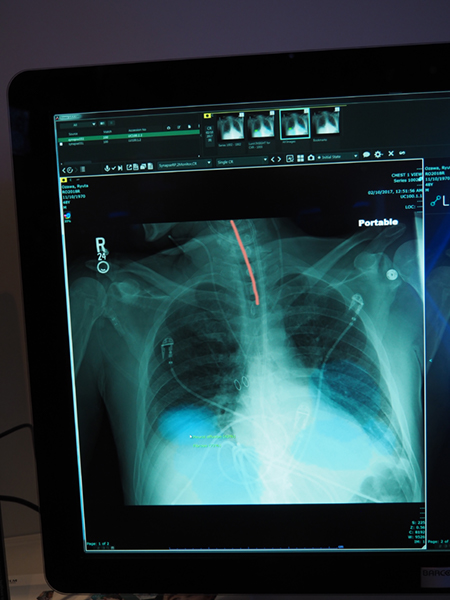

このように,富士フイルムグループのAI環境のコンセプトは,データの入力から解析結果の出力までオープンな環境で構築されているのが特徴である。さらに,読影システムへの実装では,従来の環境はそのままに,AI利用のために新たな操作方法などをおぼえることなく使えるシステムをめざしているのも特徴だ。現状でデモに搭載されているアルゴリズムは,自社開発の脳卒中(脳内出血,くも膜下出血,脳梗塞)や肺がんなどの7つと,Lunit(胸部X線画像から4つの疾患を検出するアルゴリズム)Riverain Technologies,Koios Medicalのサードパーティ製,UCLAで開発されたカテーテルの自動検出アルゴリズムで,自社だけでなくさまざまなアルゴリズムが一つのプラットフォームに統合されている。

胸部X線画像ではサードパーティのAIアルゴリズムで解析した結果をオーバーレイで表示